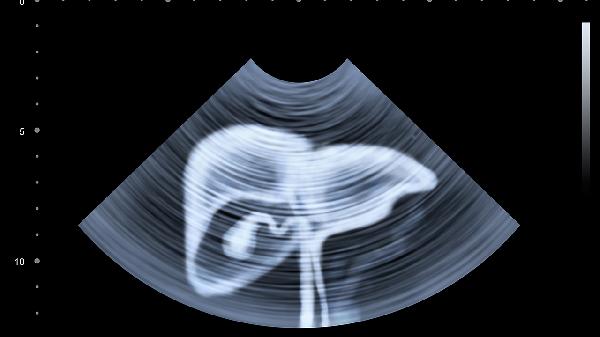

肾结石移动过程中划伤输尿管黏膜可能造成血尿,误认为便血。结石嵌顿引发下腹绞痛并向腰骶部放射。金钱草、海金沙等中药可促进排石,推拿按摩肾俞、膀胱俞穴位配合跳跃运动帮助结石排出。疼痛剧烈需及时就医进行体外碎石。